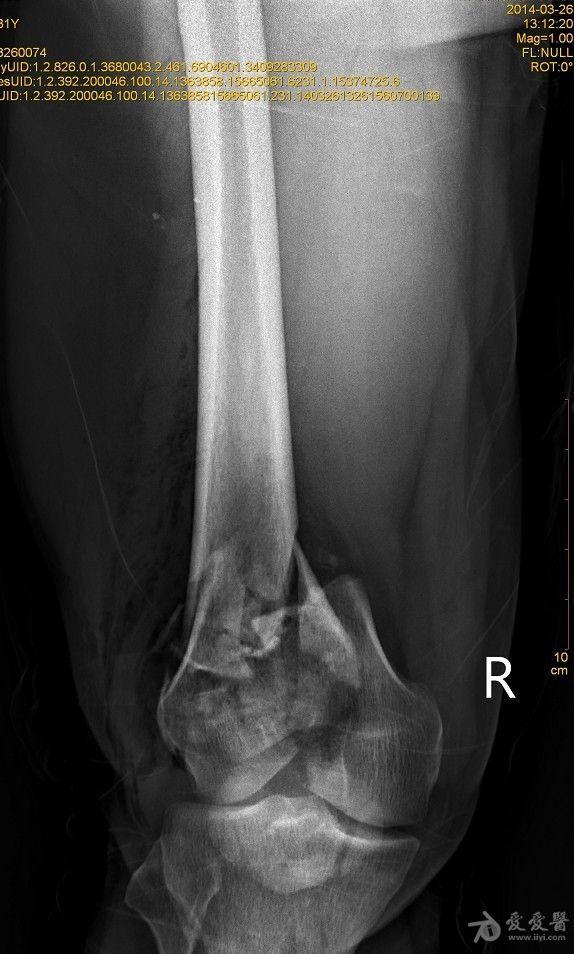

右股骨远端开放性粉碎性骨折

患者XXX,男,31岁,农民。高空跌伤致右大腿畸形伴活动性出血1小时入院。患者一般情况可,体重80kg。完善相关辅检,入院诊断:1.右股骨远端开放性粉碎性骨折;2.右髌骨粉碎性骨折;3.右桡骨远端骨折。入院后行右股骨开放性骨折清创缝合术+右胫骨结节骨牵引术,布朗支架抬高制动,目前患者右大腿远端肿胀明显,给予抗感染,消肿止痛等对症支持治疗。 2014-3-19,爱爱医***里mimi98发了类似的帖子,我刚好也遇到了同样的病例,诚心向各位老师、战友寻求好的治疗方案。